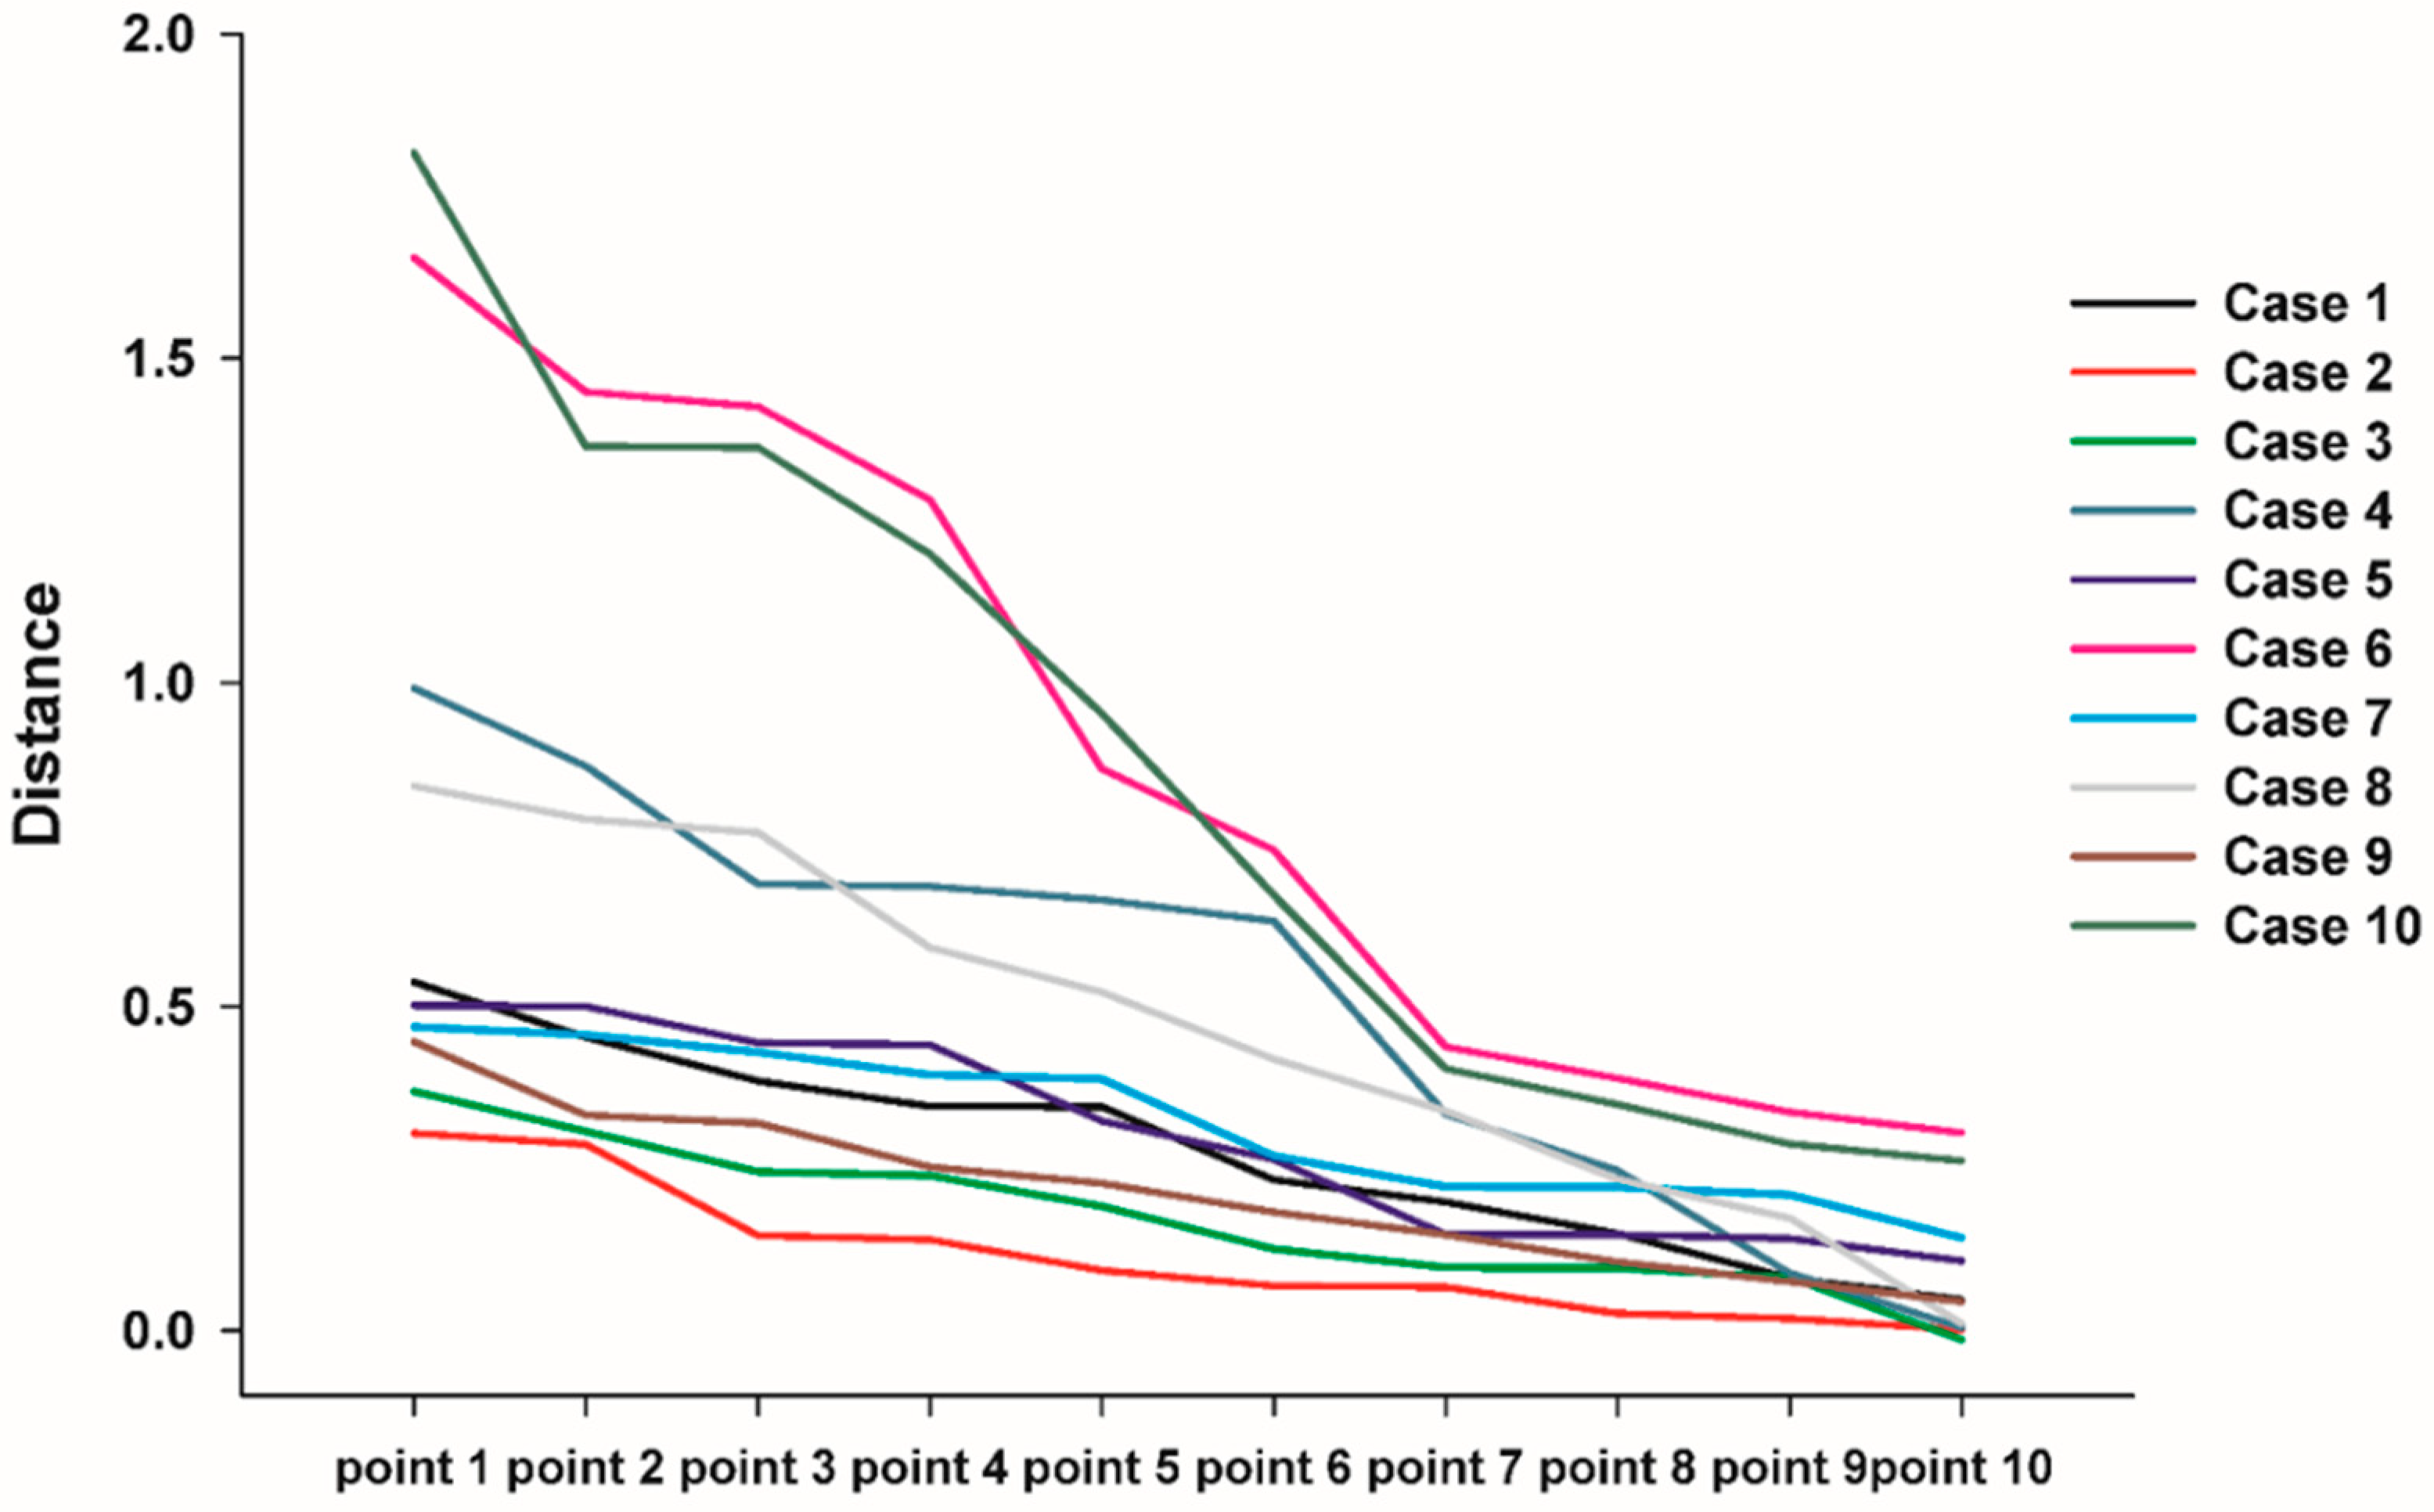

3.3. 3D Comparison between Immediate Post Operative and 6 Months Post Operative

| Point 1 | 2 | 3 | 4 | 5 | 6 | 7 | 8 | 9 | 10 | Aver. | SD | |

|---|---|---|---|---|---|---|---|---|---|---|---|---|

| Case 1 | 0.3853 | 0.3461 | 0.5375 | 0.3455 | 0.4526 | 0.233 | 0.1499 | 0.1982 | 0.0476 | 0.0812 | 0.2776 | 0.1616 |

| 2 | 0.1469 | 0.3044 | 0.0014 | 0.2874 | 0.0191 | 0.1403 | 0.0927 | 0.0263 | 0.0695 | 0.0675 | 0.1155 | 0.1064 |

| 3 | 0.0979 | 0.0137 | 0.1259 | 0.0966 | 0.0821 | 0.1918 | 0.2396 | 0.3076 | 0.2452 | 0.3689 | 0.1741 | 0.1170 |

| 4 | 0.3342 | 0.0045 | 0.0888 | 0.2472 | 0.6319 | 0.6853 | 0.6889 | 0.6646 | 0.871 | 0.9915 | 0.5207 | 0.3327 |

| 5 | 0.1479 | 0.3236 | 0.1486 | 0.1077 | 0.4406 | 0.1422 | 0.5004 | 0.4437 | 0.5019 | 0.2645 | 0.3021 | 0.1602 |

| 6 | 0.4378 | 0.3892 | 0.337 | 0.3052 | 0.8668 | 0.7413 | 1.2819 | 1.4485 | 1.4251 | 1.6551 | 0.8887 | 0.5231 |

| 7 | 0.4298 | 0.2216 | 0.3879 | 0.2224 | 0.2695 | 0.2097 | 0.4689 | 0.3944 | 0.1436 | 0.456 | 0.3203 | 0.1192 |

| 8 | 0.4187 | 0.3392 | 0.5911 | 0.8404 | 0.5219 | 0.7681 | 0.7887 | 0.2335 | 0.1735 | 0.011 | 0.4686 | 0.2826 |

| 9 | 0.3199 | 0.1057 | 0.2524 | 0.1483 | 0.2272 | 0.3322 | 0.1833 | 0.4457 | 0.0755 | 0.045 | 0.2135 | 0.1270 |

| 10 | 0.3489 | 0.2618 | 0.9525 | 0.4041 | 0.288 | 1.3645 | 1.1981 | 0.6722 | 1.8174 | 1.3628 | 0.8670 | 0.5513 |